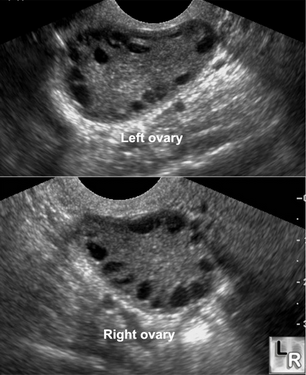

Hình ảnh siêu âm của bệnh nhân mắc hội chứng đa nang buồng trứng.

Phụ nữ bị buồng trứng đa nang thường là những người có sự gia tăng bất thường về nồng độ testosterone và LH,  những chất này sẽ làm gián đoạn quá trình phát triển của nang noãn. Buồng trứng xuất hiện nhiều nang nhỏ (từ 6 - 10 nang < 10mm) do nang noãn không phát triển được, trứng không thể trưởng thành và không có hiện tượng rụng trứng.